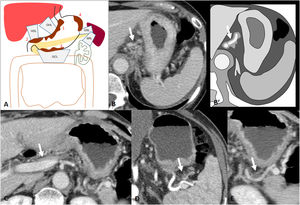

A direct malignant invasion of the perigastric veins or invasion through the perigastric veins extending beyond the wall of the gastrointestinal tract is known as extramural venous invasion (EVI). Histologically, it is defined as the presence of tumour cells in veins beyond the muscularis propria, and although its diagnosis is primarily histological, advances in imaging techniques such as MDCT have made it possible to assess the existence of EVI prior to surgery50. It is frequently associated with extramural periarterial, perineural and lymphatic invasion. It is not a criterion of the AJCC system, but is considered a poor prognostic factor, associated with increased recurrence and shorter survival time51–53

There are 3 types of EVI. a) intraluminal (the most frequent): tumoural spread within the vessel (tubular configuration of the vessel), sometimes distending it; b) floating: tumour within the lumen but with free-floating edges; and c) infiltrative: the tumour infiltrates the vessel wall by contiguity50. EVI is typically seen on CT as a tubular or nodular soft-tissue thickening extending from the tumour along the perigastric vessels50. Multiplanar reconstructions or Maximum Intensity Projection (MIP) can be helpful in assessing EVI (Fig. 9). The detection of EVI by CT has been shown to be an independent predictor of poor survival in patients with AGC52,53.

Extramural venous invasion. A) Illustration of the gastric venous system. B) Diffuse gastric adenocarcinoma with EVI of the left gastric vessels in the gastrohepatic ligament (arrow). C) Same case as in B with MIP reconstruction of the arterial phase, where the tubular thickening of the left gastric vein is more evident.